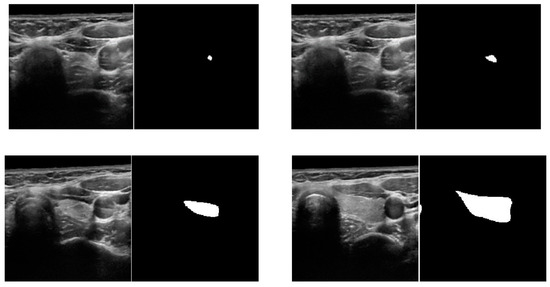

4.1. Experimental Datasets

4.2.2. Data Augmentation